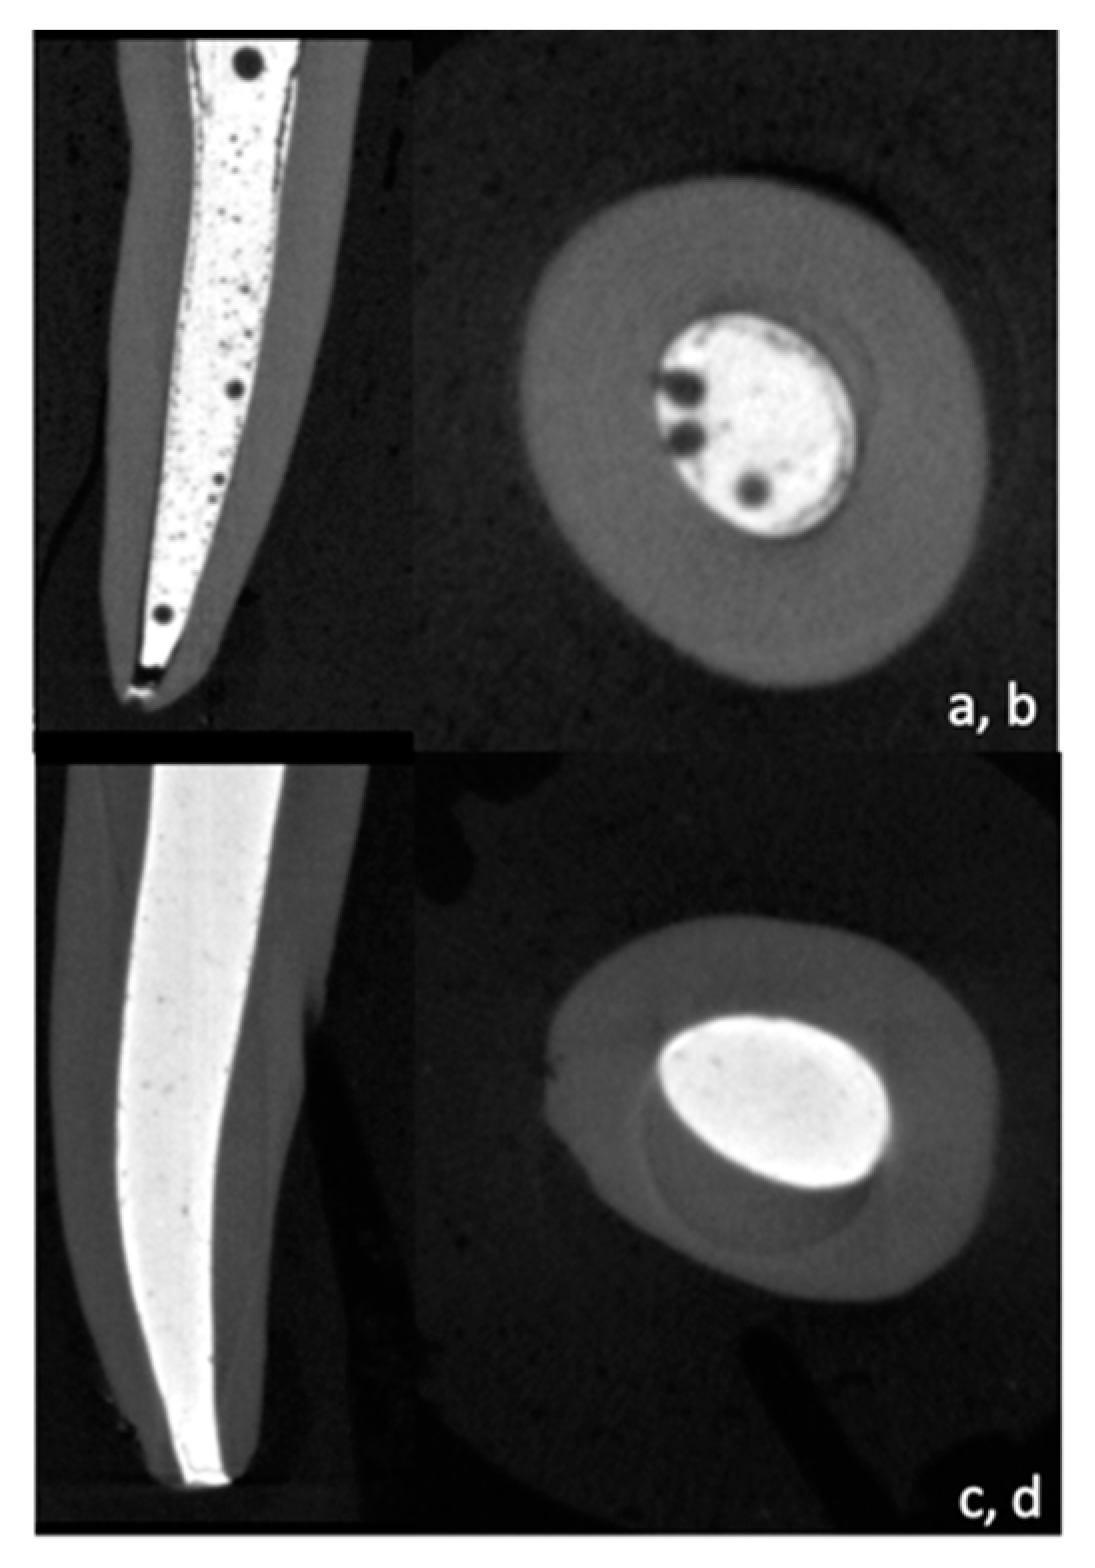

The percentage of filling and voids was evaluated using a threshold method and 3D models in the coronal, middle, and apical sections (Figure 1).

Figure 1.

Micro-CT cross sections and reconstructed 3D image showing Bio-C Pulpecto (a,b) and ZOE (c,d).

The first methodology adopted in this study to compare the filling ability of ZOE and Bio-C Pulpecto was micro-CT imaging. Micro-CT is used to analyze tooth structure objectively, allowing for quantitative and qualitative image analysis [33,34]. Additionally, it enables the accurate reconstruction of 3D models and can distinguish between tooth structures, voids, and obturation materials [35]. Both materials produced voids in all canal thirds, with Bio-C Pulpecto revealing higher void percentages than ZOE (10.3 ± 3.8%, and 3.5 ± 1.3%). This was per the results of numerous studies, regardless of the filling material, that agree on the difficulty of achieving a void-free obturation due to the complex root canal anatomy of human teeth [36,37].

In addition, in primary dentition, the obturation relies exclusively on a resorbable filling paste, without the support of a gutta-percha cone, which renders the 3D obturation even more difficult, especially with the abundance of lateral canals, isthmus, and canal curvatures [32,38]. In one of the few previous micro-CT studies on primary teeth filling, the authors suggested that using a syringe to inject the paste produced fewer voids than using a lentulo spiral [7]. This could explain why, in this study, there was an increase in apical voids for the ZOE group (p < 0.05), whereas there was no discernible difference between coronal, middle, and apical thirds for the Bio-C Pulpecto group (p > 0.05). In fact, in an attempt to enhance the quality of root canal obturation on primary teeth and decrease the void volume, some authors proposed ultrasonic activation of the filling paste for a better infiltration in the intricate primary teeth anatomy [39]. More micro-CT studies should be conducted to find the most efficient filling technique for primary teeth.